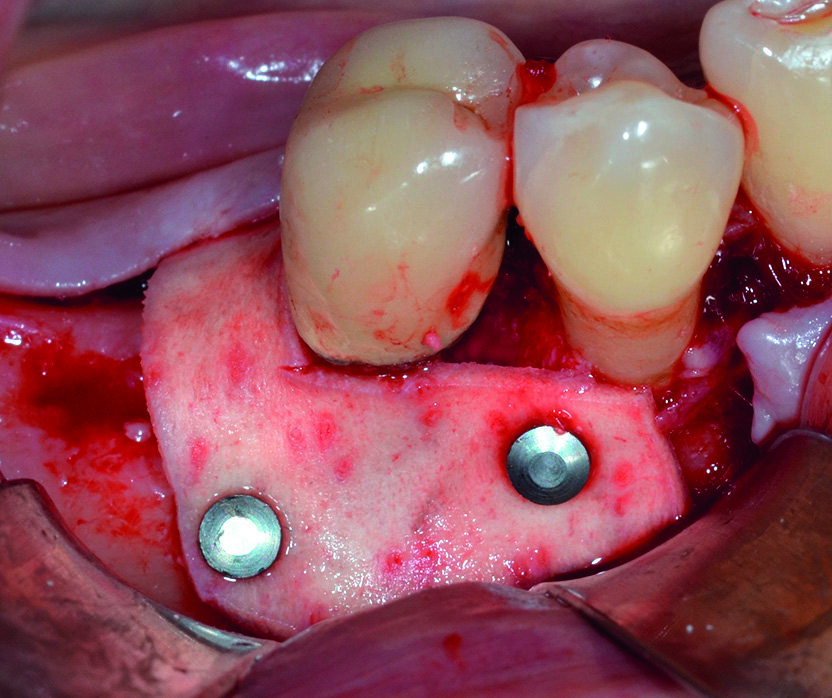

La componente intraossea del difetto viene innestata con un particolato di origine eterologa, allo scopo di favorire il mantenimento dello spazio necessario alla rigenerazione e migliorare la stabilità del coagulo (Fig. 14). Dopo un’adeguata compattazione del biomateriale, la membrana viene quindi riflessa sul versante buccale e fissata per mezzo di pins in titanio; contestualmente all’ intervento di GTR viene anche inserito un impianto osteointegrato in zona 4.6 (Fig. 15).

Al momento del controllo a 8 mesi vengono esaminate le condizioni dei tessuti parodontali marginali e si effettua una radiografia endorale periapicale, che evidenzia la completa risoluzione del difetto intraosseo (Figg. 17, 18). Incidentalmente, in occasione della scopertura dell’impianto precedentemente inserito, si sceglie di constatare de visu la rigenerazione ottenuta intorno all’ elemento 4.5: al sollevamento del lembo è possibile apprezzare la completa risoluzione del difetto intraosseo circonferenziale, a conferma di quanto già emerso dal controllo radiografico (Figg. 19, 21). Dopo aver esposto la testa dell’impianto in zona 4.6 si rimuove la vite di copertura, che viene sostituita con un healing abutment di adeguate dimensioni (Figg. 22, 23).